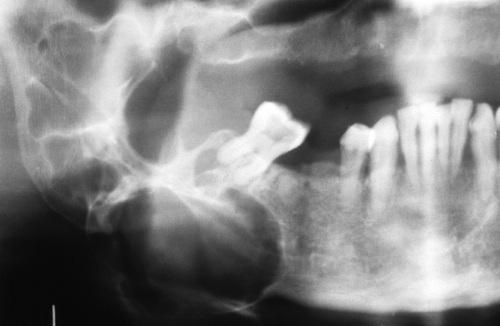

Radiopaque mass located at the left angle of the mandible. They may be discovered anywhere along the length of the duct or within the gland itself.

sialolith